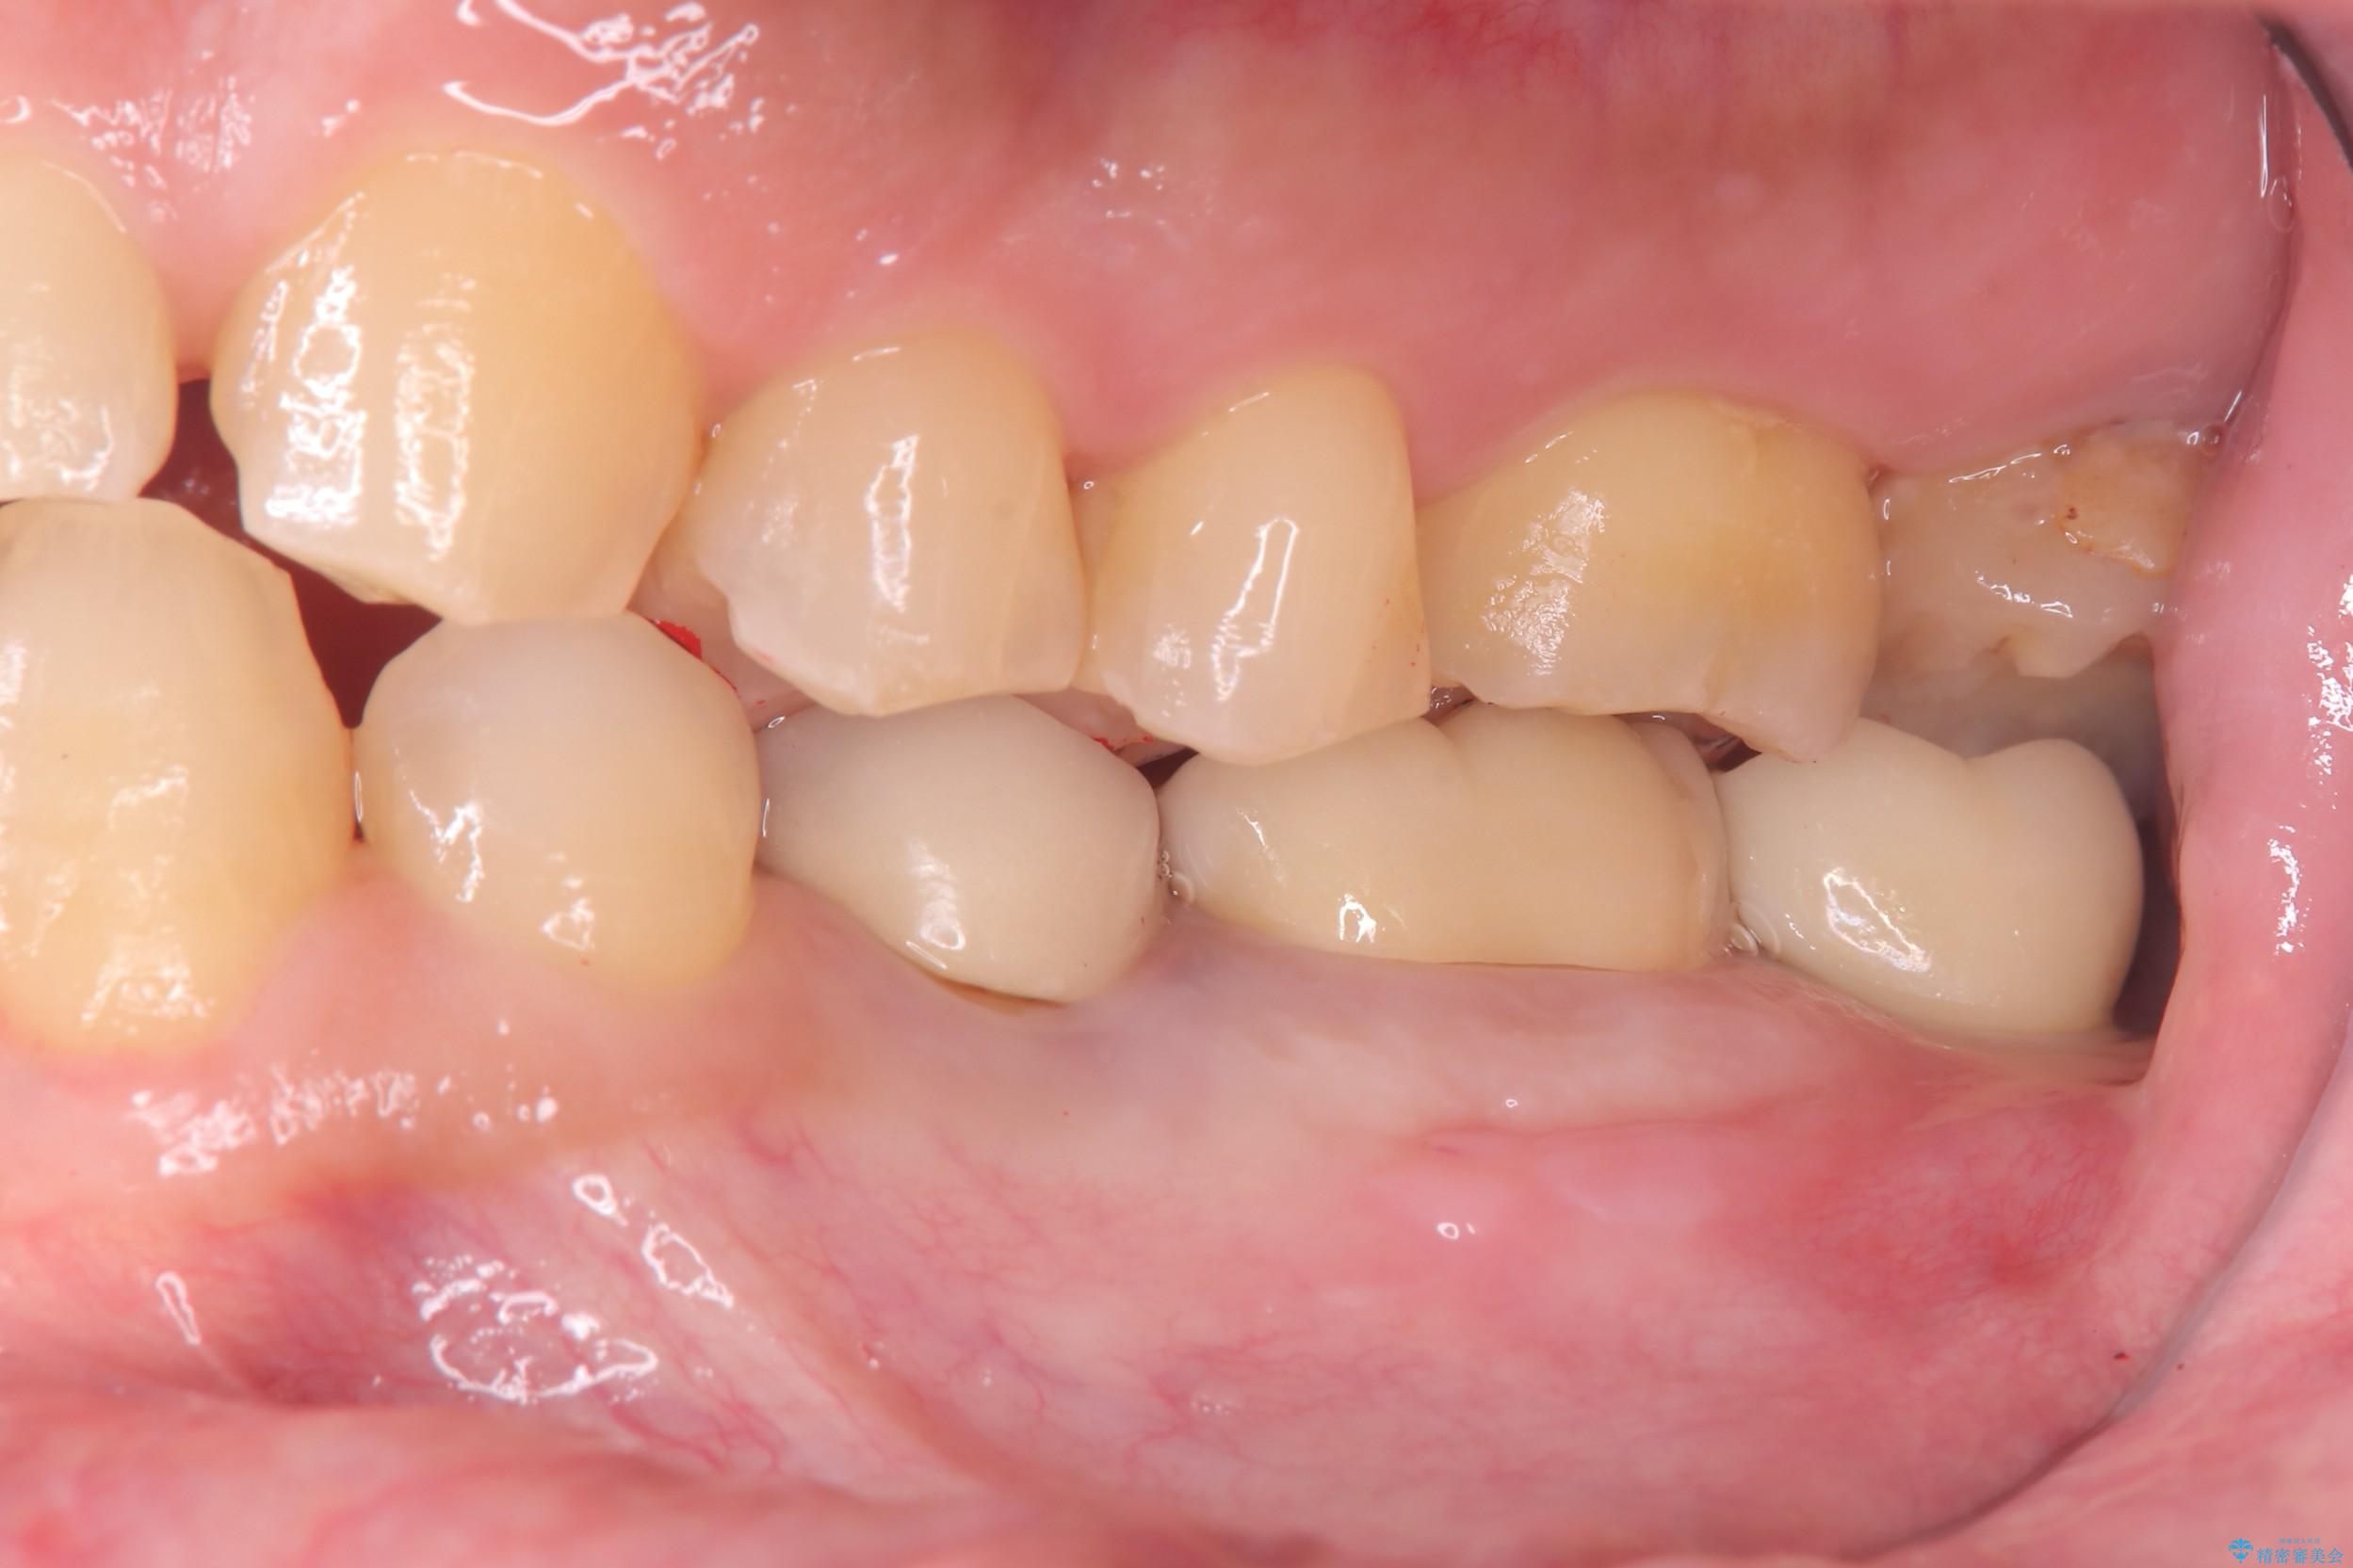

抜歯と同時にインプラントを埋入するため、歯茎を切開する必要がなく、術後の痛みが出にくい治療方法です。

手術は1回で完了し、被せ物を装着するまでの治療期間も約3か月と、身体的・時間的な負担を抑えることができます。

今回の患者様も、治療直後に痛み止めを1錠服用されたのみで、その後は痛みが出ることなく、追加の服用は不要だったとのことでした。